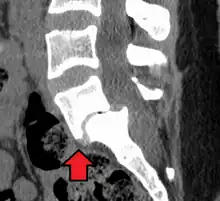

MRI of L5-S1 anterolisthesis -

Anterolisthesis L5/S1 -

Anterolisthesis L5/S1. Blue arrow normal pars interarticularis. Red arrow is a break in pars interarticularis -

Anterolisthesis L5/S1

MRI

Magnetic resonance imaging (MRI) is the preferred advanced imaging technique for evaluation of spondylolisthesis.[26] Preference is due to effectiveness, lack of radiation exposure, and ability to evaluate for soft tissue abnormalities and spinal canal involvement.[26][27] MRI is limited in its ability to evaluate fractures in great detail, compared to other advanced imaging modalities.[28]